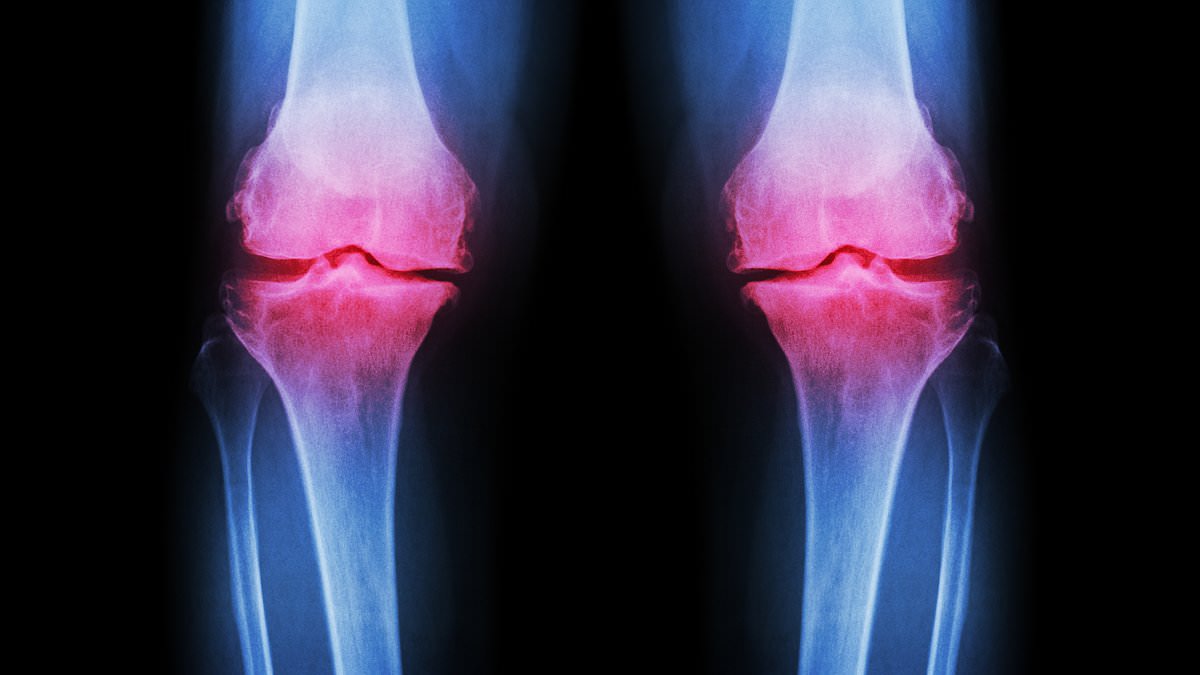

Osteoarthritis, a condition affecting millions globally, is typically associated with aging. Yet, its presence is now being diagnosed in younger populations at an unprecedented rate. By the age of 70, roughly half of all individuals will develop arthritis, but experts warn that the trend is shifting. In the UK alone, around 10 million people live with osteoarthritis, and younger generations are increasingly being affected. The condition arises when the cartilage that cushions joints deteriorates, leading to pain, stiffness, and mobility issues. While factors like genetics, obesity, and injury contribute to this decline, the role of extreme exercise and poor dietary habits in accelerating the process cannot be overlooked.

Post-traumatic osteoarthritis, a subset of the condition, often results from fractures that extend into joints. These injuries can disrupt normal joint mechanics, causing cartilage to break down more rapidly. However, unlike osteoporosis—where fragile bones significantly increase fracture risk—osteoarthritis can be mitigated through lifestyle adjustments. The challenge lies in the fact that many young people remain unaware that their exercise and diet choices can exacerbate their risk. For instance, the exclusion of dairy products in 'clean eating' diets is leading to calcium deficiencies, which weaken bones and increase inflammation.